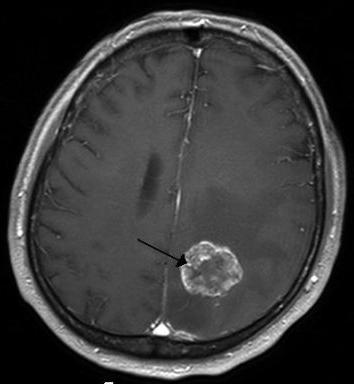

Кроме рентгенографии можно сделать МРТ, КТ. Эти методы позволяют обнаружить опухолевое тело и понять, где оно располагается, можно ли его удалить. Доброкачественная или злокачественная ОГМ можно определить, только проведя биопсию или взяв пункцию спинномозговой жидкости.

МРТ

Сначала приходится установить, где именно находится опухоль. Это помогает сделать МРТ или КТ головного мозга. Томография показывает, где находится новообразование, каков его размер, есть ли рядом с ним участки отмерших тканей (некроз) и следы кровоизлияний. Также с помощью томографии определяют, насколько сильно опухоль повредила окружающие ткани.

Много информации об опухоли дает и такой вид диагностической процедуры как позитронно-эмиссионная томография (ПЭТ). В ее ходе производится отслеживание, как перемещается в мозгу радиоактивный меченый сахар. Быстро делящиеся клетки опухоли поглощают его значительно быстрее, чем здоровые ткани. ПЭТ часто назначают в качестве дополнения к МРТ или КТ.

Для того чтобы оценить состояние кровеносных сосудов, питающих опухоль, делается МРТ-ангиография. А спинномозговая пункция позволяет установить наличие в ней особых онкомаркеров или даже самих раковых клеток.